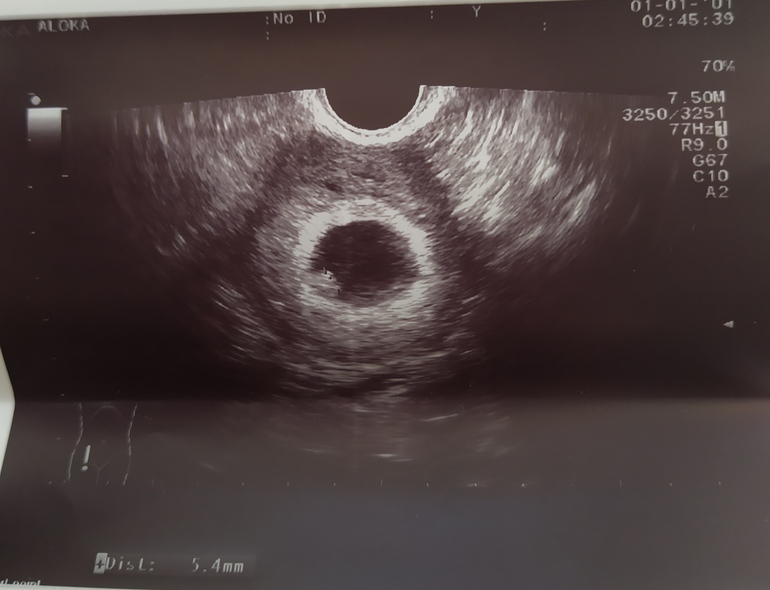

Подскажите мне?🙏🏻Делали вагинально)

15.02.2021

Екатерина Семёнова, ой я не разбираюсь, по мне похоже на мальчика, если сравнивать с моим. Спросите у девочек, кто владеет этими знаниями определения)

16.02.2021